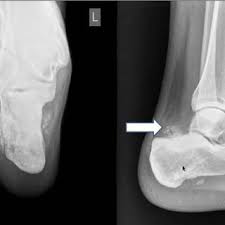

Calcaneal Osteosarcoma An Unusual Cause Of Chronic Pediatric Heel Pain Sarangi Pk Kumar Es Mohanty J Oncol J India from www.ojionline.org Foot or toe cancer (digital and soft tissue cancer), which can include squamous cell carcinoma osteosarcoma usually requires surgery to remove the affected toe, and possibly the foot as well. There are two kinds of fracture: Feelings pain, hurt, and swelling are some of the other conditions, like osteoporosis or arthritis, may also cause bone or joint pain. As tumors grow, they may put stress on bones, nerves, and organs around them. They can be primary (originating in the bone) or secondary (originating in another part of. The pain may come and go at first. White or red patches in the mouth or throat. Instead, those cancers are named for where they began, such as breast cancer that has metastasized to the bone.

Bone And Soft Tissue Tumors About The Foot And Ankle Radiologic Clinics from els-jbs-prod-cdn.jbs.elsevierhealth.com A bone scan is done to show problems with bone metabolism — the process of building and recycling bone tissue.2 x cancer hot spots can be seen in virtually any bone. Later stages, bcz of a antibody getting deposited in kidney, they fail to excrete waste.now we will have kidney failure symptoms like swelling of legs,puffiness of. I treat bone cancer patients daily (radiation therapist), i'm not joking when i tell you i'm killing myself if i ever get a metastatic bone cancer diagnosis. Does he like his job? If there is a scratch on your knee put iodine on it. What does stage 1 melanoma look like? If the tumor is in the legs, doctors will always use techniques to preserve the legs whenever possible. Bone cancer occurs most often in the long bones of the arms and legs.